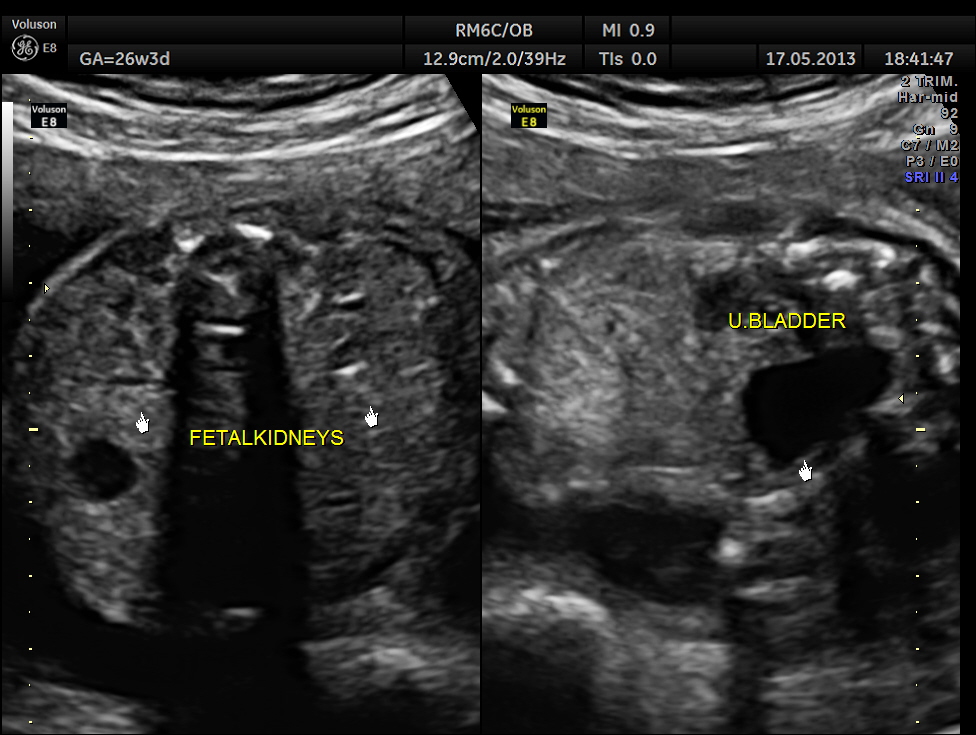

The abdominal images are given below.

The limbs are shown below.